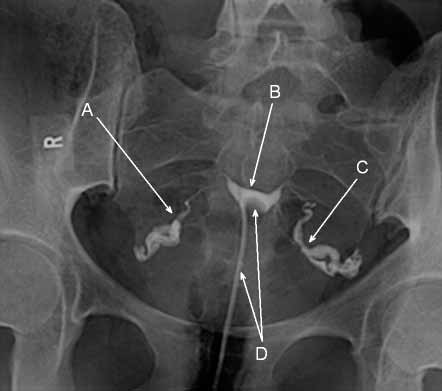

Медицинские снимки: Проходимость маточных труб